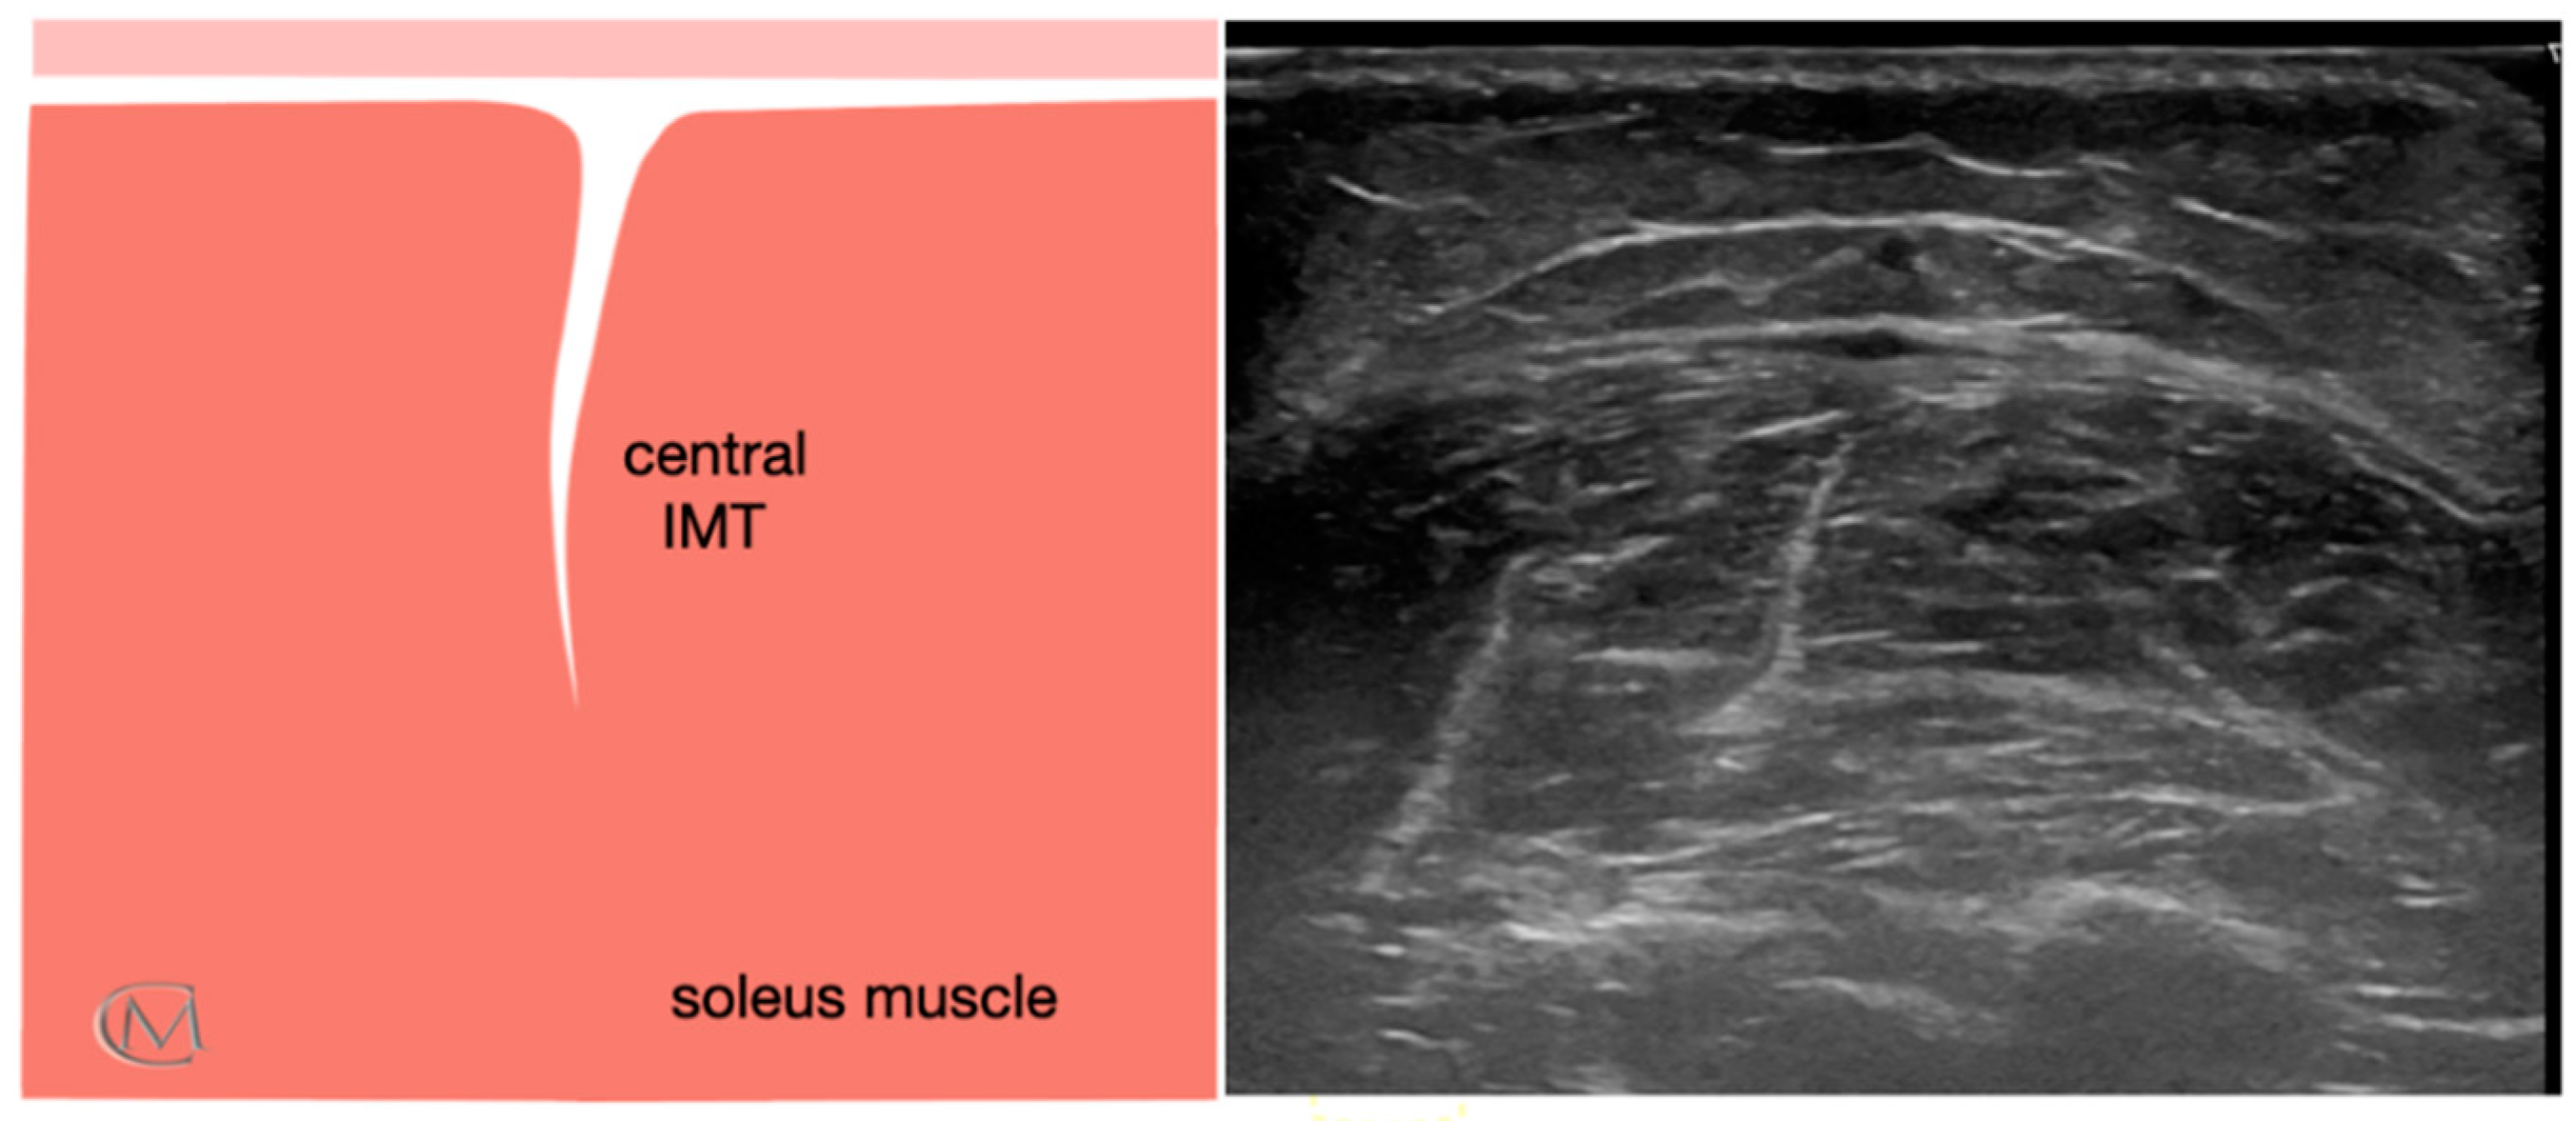

Echotexture features of the soleus muscle were reviewed for 84 subjects. They were divided based on the muscle echogenicity in three groups: Injury Type 1 group, healthy group (Figure 1), Injury Type 1 and Injury Type 2 (Figure 2). As in previous studies [7,24], a central IMT tear in the soleus muscle was identified when patients reported having symptoms for at least six months, and they established a self-rated progressive stiffness value greater than or equal to 4 points during sports exercises or during the soleus stretching, measured using the numeric rating scale (NRS) [25]. The enrollment was carried out in a private clinic specialized in sports injuries. First of all, researchers filled out the clinical history of the subjects. The presence of a central IMT injury of the soleus muscle was determined according to the following criteria: clinical history of the individuals, clinical evaluation performed by an experienced therapist and US examination carried out by an US-imaging specialist clinician with more than 15 years of experience.

Figure 1.

Ultrasound image of soleus muscle in healthy athletes. It shows a normal central IMT. Left panel: anatomic diagram of soleus muscle; Right panel: ultrasound image of the soleus muscle; Abbreviations: IMT, central intramuscular tendon.

Echointensity and echovariation were taken in all groups like quantitative US variables. The imaging study was performed offline with the ImageJ software (Bethesda, MD, USA) by a blinded tester. According to previous study [7], a range of interest (ROI) of 64 × 64 with an 8-bit gray scale using the ROI Manager tool was executed to extract the pixel distribution histogram. The ROI was considered as the muscle area without bone and fascia with the best reflection (Figure 1). Subsequently, echotexture values were captured from the histogram where EI was considered as the mean value of the gray-scale distribution of the pixels, and EV was described as the relation between SD and the mean of pixel distribution (EV = σ/μ × 100), where σ is the SD of the image intensities and μ is the mean value of intensity in each ROI of the three images previously recorded.